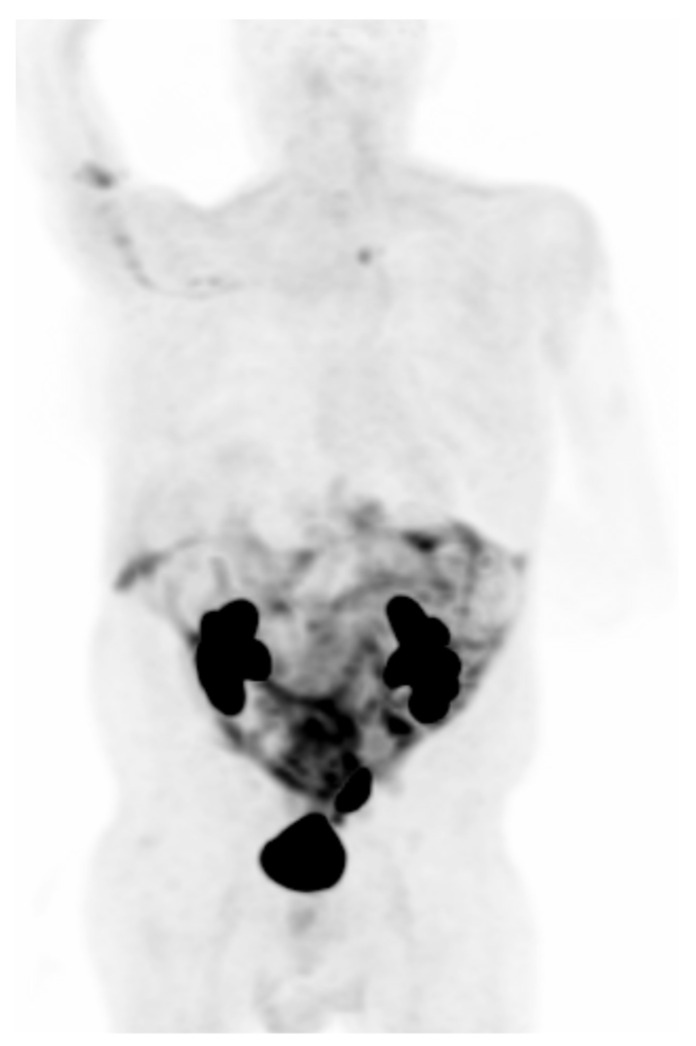

Figure 5.

Is a representative 68Ga-FAPI maximum intensity projection, negative for malignancy, showing the physiologic uptake of this tracer.